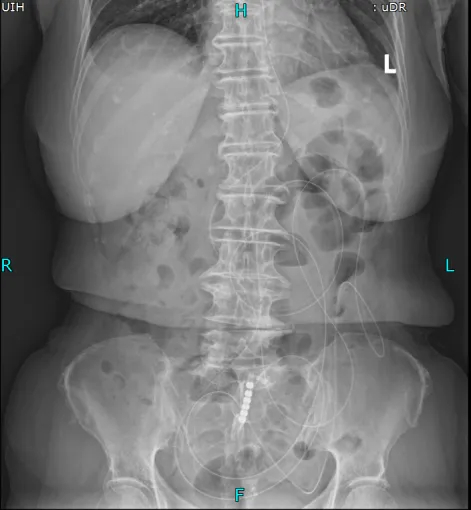

置入导管后肠梗阻明显减轻

考虑到王奶奶疼痛难忍、无法移动,普外科团队直接将胃镜设备推至病房床边,不到10分钟就完成了肠梗阻导管置入术。这根长达280cm的特殊导管不仅快速缓解了王奶奶的胀痛,还为后续治疗争取了关键时间,也为手术提供了安全保障。